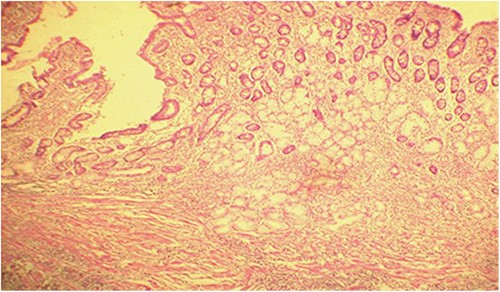

Microscopic analysis of various samples showed a transparietal massive infiltration of eosinophils with over 25% epithelial exocytosis and no granulomatous lesions or parasitic agents (Figs 3 and 4). Lymph nodes sampled from the congestive mesentery were reactive. The diagnosis of eosinophilic enteritis was established. The postoperative course was rapidly favorable, with weight gain. The patient was readmitted, and etiological assessment as well as a search for other locations, including hepatic and osteomedullary biopsies, returned negative results.

Intraepithelial exocytosis of eosinophilic polymorphonuclear leukocytes (hematoxylin–eosin staining, magnification × 200).